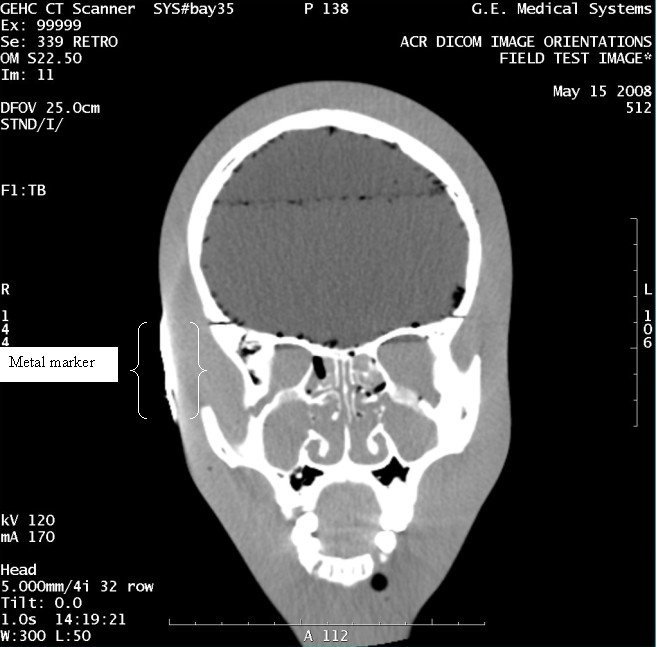

- With the support of the site personnel, examine the images sent

to the Review Station (i.e., 12 series, each with 1 image) and compare

their orientation to the images in this document.

- Each image contains a metal marker on the phantom's right cheek.

- Each image in this document contains a description of the expected

orientation of the metal marker (i.e. to prove Left and Right) as

well as the Posterior and Anterior orientation description.note:

The sample images included in this document use “R”, “L”, “P”, and “A” for “Right”, “Left”, “Posterior” and “Anterior” orientation. The Hospital Review Station may use a different style of annotation. The style used is not relevant to this procedure.

- Each image in this document has sufficient space to store the observed results for up to 4 Review Stations.

- Enter ‘Y’ in the space to indicate the observed result matches the expected.

- Enter ‘N’ in the space to indicate the observed result does not match the expected.

- Enter “NA” in the space if a column is not being used.

- Repeat for each destination.

Figure 9. Exam 99999, Series 339